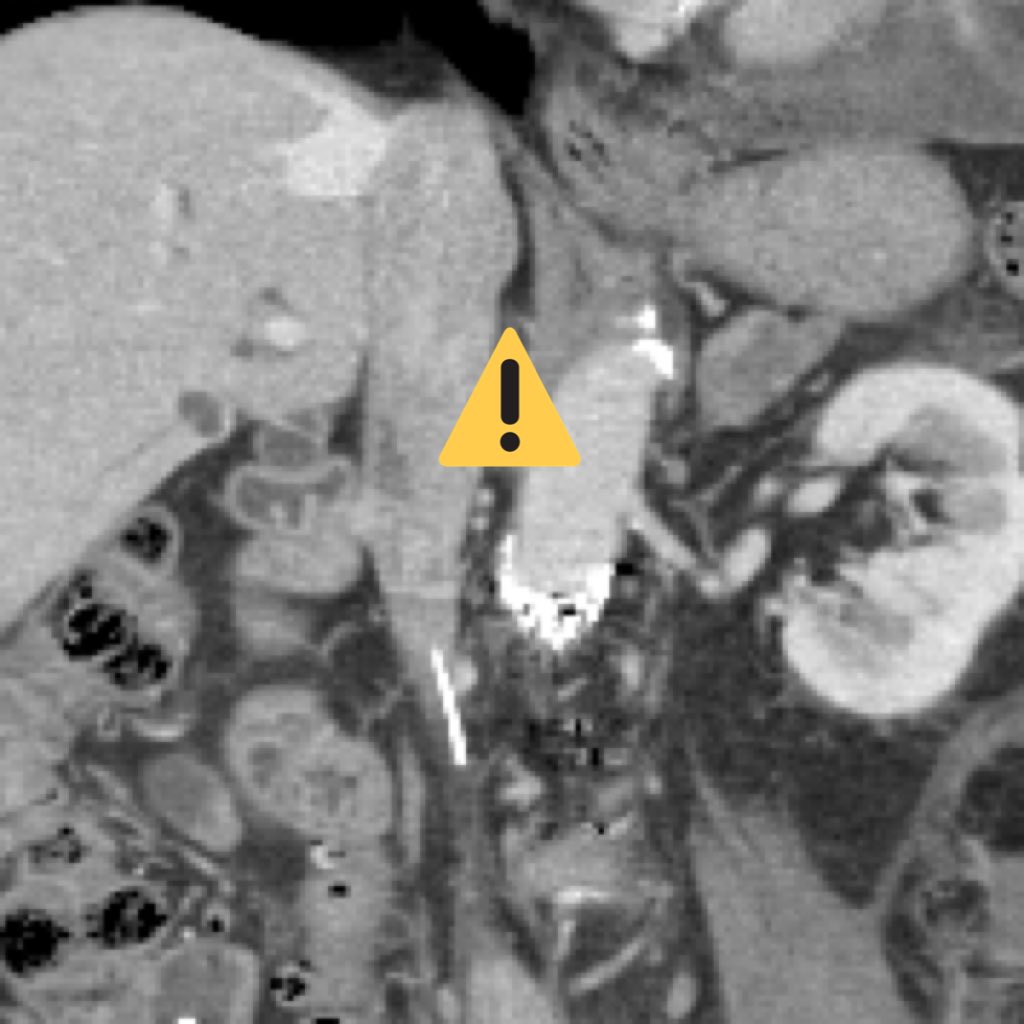

Friendly reminder to get that #IVCFilter out when no longer needed. This patient had acute thrombosis of her IVC and right iliac veins 2.5 years after placement. Clean as a whistle after @BostonPIMedEd #AngioJet thrombectomy and tPA Thrombolysis w #FilterOut. 2 year f/u CT #iRad